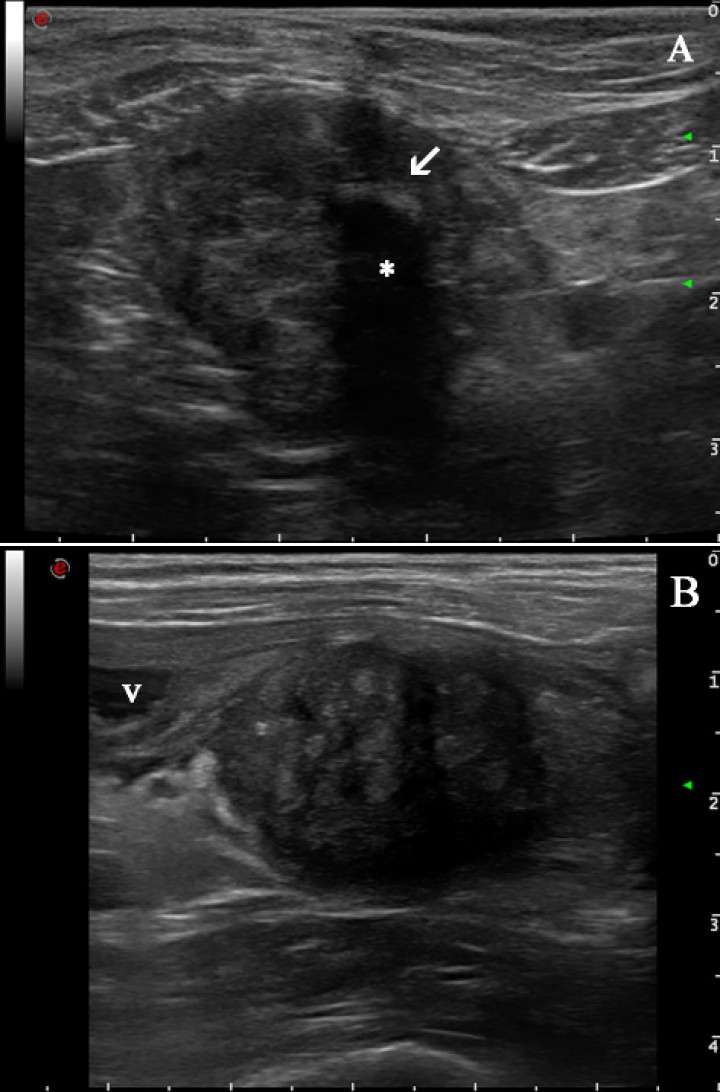

En el examen ecográfico del abdomen se observó, caudal a la vejiga de la orina y ventral al colon descendente, una masa redondeada bien delimitada con bordes irregulares de aproximadamente 3 cm de diámetro, de ecotextura heterogénea y ecogenicidad mixta, moderadamente vascularizada. En su interior se visualizó una estructura hiperecogénica de 0,6 cm de longitud que producía sombra acústica (Fig. 1A). El aspecto ecográfico de la vejiga era normal, con contenido anecogénico. El resto de las estructuras abdominales tampoco presentaban alteraciones ecográficas evidentes.

<p>Imágenes ecográficas de la masa en diferentes momentos de presentación. (<strong>A</strong>) Día de la presentación: Masa redondeada, bien definida de ecotextura heterogénea y ecogenicidad mixta caudal a la vejiga de la orina y en cuyo interior se visualiza una estructura hiperecogénica (flecha blanca) que proyecta sombra acústica (asterisco). (<strong>B</strong>) Imagen obtenida un año más tarde donde se observa una masa de similares características a la figura 1A. v: vejiga de la orina.</p>

Imágenes ecográficas de la masa en diferentes momentos de presentación. (A) Día de la presentación: Masa redondeada, bien definida de ecotextura heterogénea y ecogenicidad mixta caudal a la vejiga de la orina y en cuyo interior se visualiza una estructura hiperecogénica (flecha blanca) que proyecta sombra acústica (asterisco). (B) Imagen obtenida un año más tarde donde se observa una masa de similares características a la figura 1A. v: vejiga de la orina.

Con los hallazgos ecográficos y con su historial de perra castrada donde se utilizó seda como material para la ligadura de los pedículos ováricos y uterino, el diagnóstico presuntivo más probable fue de granuloma por cuerpo extraño del muñón uterino, siendo otros diagnósticos diferenciales menos probables hematoma, absceso o neoplasia. Para alcanzar el diagnóstico definitivo se practicó una punción ecoguiada con aguja fina de la masa y el estudio citológico reveló un proceso inflamatorio no séptico. Por lo tanto, el diagnóstico más probable fue el de granuloma por cuerpo extraño en el muñón uterino. Se recomendó la resección de la masa, la cual se realizó en la clínica veterinaria de origen.

Un año más tarde, la paciente fue remitida para un examen ecográfico porque presentaba polaquiuria y en la analítica sanguínea unos valores de creatinina levemente aumentados (1,53 mg/dl; rango normal: 0,7 a 1,4 mg/dl). El resto de los parámetros se encontraron dentro de los valores de referencia. En la evaluación ecográfica se visualizó una masa de características similares a la observada un año antes y en el mismo lugar (Fig. 1B) de 2,5 cm de diámetro. Además, la pelvis renal y divertículos del riñón izquierdo se encontraban marcadamente dilatados por líquido anecogénico con una mínima remanencia de la corteza renal (Fig. 2A). El uréter ipsilateral también estaba severamente dilatado en todo su trayecto con contenido anecogénico, midiendo 1,65 cm de diámetro y pudiendo seguir su recorrido hasta la masa en la que se encontraba involucrado (Fig. 2B). El riñón derecho presentaba un aspecto normal (Fig. 2C). El diagnóstico presuntivo fue de hidronefrosis e hidrouréter izquierdo severo debido a compresión del uréter izquierdo por parte de un granuloma por cuerpo extraño en el muñón uterino.

El diagnóstico de los granulomas debido a cuerpos extraños puede ser un reto, sobre todo cuando se presentan mucho tiempo después de haberse realizado la cirugía. La radiografía o la ecografía pueden ser las primeras técnicas de imagen que utilicemos según la sintomatología que manifieste el paciente. En este caso, en la radiografía realizada por el veterinario remitente se observó una masa en el abdomen caudal. Debido a que en la radiografía no podemos diferenciar el líquido del tejido blando, ya que presentan la misma opacidad, si se observan masas en el abdomen se recomienda realizar una ecografía para caracterizar mejor el aspecto que presentan dichas masas.[ Boza S, Lucas X, Zarelli M, et al: Late abscess formation caused by silk suture following hysterectomy in a female dog. Reprod Domest Anim 2010; 45(5): 934-936. [pubMed] , Erdoğan G and Yaygıngül R: Clinical Features and Surgical Outcomes of Suture Granulomas Following Ovariohysterectomy in Two Dogs. Animal Health Prod and Hyg 2020; 9(1): 703-706. ] En nuestro caso, en la ecografía se visualizó una masa bien delimitada de márgenes irregulares, de ecotextura heterogénea, ecogenicidad mixta y moderadamente vascularizada. Además, en el primer estudio se observó una estructura hiperecogénica central que producía sombra acústica compatible, lo más probable, con un resto de la sutura de seda o con una mineralización distrófica de los tejidos en esa zona. También permitió visualizar las alteraciones que se habían producido a nivel de los riñones y uréteres.